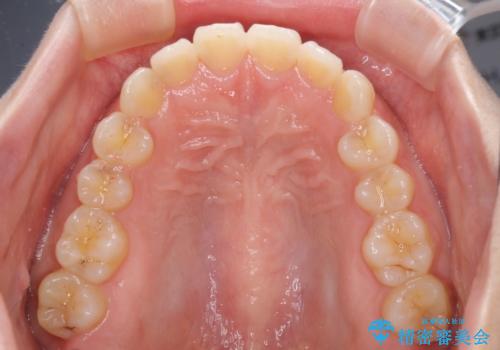

- 前歯のデコボコを治したいとのことで来院された患者様です。

上下顎ともに歯列全体の側方拡大とIPR(歯と歯の間を削る)によってデコボコが解消するように設計し、インビザラインにより治療を行うこととしました。

後方移動に際し、残っていた上顎の親知らずを抜歯することとしました。